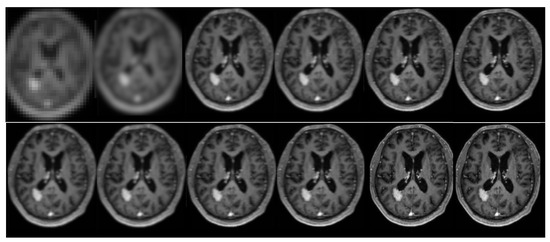

The proposed algorithmology was evaluated for its effectiveness through laboratory studies and an in vivo assessment. The main objective of this study was to evaluate and contrast the effectiveness of several super-resolution techniques and k-space sampling approaches. The efficacy of a novel technique in recreating super-resolution images was assessed by analyzing its performance relative to various cutting-edge alternatives. Additional tests were undertaken to evaluate the influence of the k-space decimation ratio on the resultant magnetic resonance (MR) images. Furthermore, a comparative analysis was conducted to examine different patterns of k-space sampling in magnetic resonance imaging (MRI). The results obtained are depicted in Figure 8 and Figure 9.

The acquired findings as depicted in Figure 8 and Figure 10, Figure 11 and Figure 12 demonstrate an enhancement in both the resolution and quality. The utilization of advanced methods for identifying potentially malignant or pre-cancerous anomalies led to improved resolution and legibility, hence enhancing the ability to detect such anomalies. Moreover, the achievements were validated by employing PSNR measures [50], which accurately evaluate the quality of medical images. This study involved an evaluation of the author’s methods in comparison to several advanced super-resolution image reconstruction algorithms. The current study focused on the reconstruction of an image using a regular sampling scheme, without the application of motion correction and SRR (1). To accomplish this, the reconstruction process involved the utilization of the B-spline curve (2) and Yang’s method [50] (3). Additionally, Lim’s method (4), Zhang’s procedure (5), Zhang’s second algorithm (6) (7), and Liu et al.’s [53] procedure (8) were employed. Lim’s method is referenced as [20], Zhang’s procedure as [51], and Zhang’s second algorithm as [18]. Furthermore, the reconstruction procedure utilized Guerreiro’s methodology [54] (9), Pham et al.’s approach [55] (10), and Shi’s method [17] (11) mentioned in the citation [20], as well as the author’s own method (12).

Figure 8. The subsequent depiction presents a clinical trial. The current study focuses on the reconstruction of an image using various techniques. In the first row, the regular sampling scheme is utilized without motion correction and SRR applied (1) (PSNR = 20.16 dB). The reconstruction process involves the use of a B-spline curve (2) (PSNR = 23.21 dB), Yang’s method [50] (3) (PSNR = 26.36 dB), Lim’s method (4) (PSNR = 29.11 dB) as referenced in [20], Zhang’s procedure (5) (PSNR = 28.71 dB) as referenced in [51], and Zhang’s second algorithm (6) (PSNR = 29.75 dB) as referenced in [43]. In the second row, Mahapatra’s method [52] (7) (PSNR = 30.03 dB) and Wang et al.’s procedure (8) (PSNR = 30.00 dB) are employed [53]. Furthermore, the reconstruction procedure utilizes Guerreiro’s et al.’s approach [54] (9) (PSNR = 30.03 dB), Pham et al.’s method [55] (10) (PSNR = 31.41 dB), Shi’s method [17] (11) (PSNR = 31.66 dB), as well as the author’s method (12) (PSNR = 32.99 dB) [20]. In addition, a sampling strategy and motion correction techniques are employed in order to achieve the super-resolution objectives. The aforementioned procedures are implemented without the inclusion of supplementary data. The compression ratio is 50%.